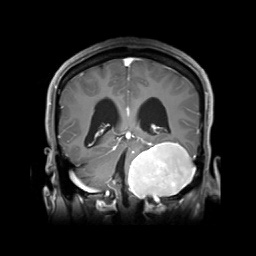

• 挑战“生命禁区”---市三医院神经外科成功完成高难度桥小脑角区肿瘤手术

挑战“生命禁区”---市三医院神经外科成功完成高难度桥小脑角区肿瘤手术 2021-02-02 患者袁女士因出现行走不稳及头晕症状,在当地医院检查颅底占位病变到我院神经外科求治;患者王先生则是因为三年前出现的右耳听力下降伴同侧面部麻木,近十天症状加重,到我院神经外科就诊。他们两人在做术前头颅MRI提示:【桥小脑角区占位病变】。大脑是人体最精密最复杂,也是…